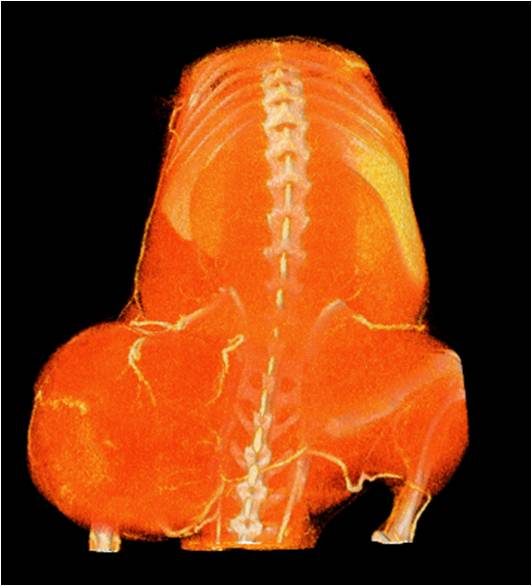

心血管

胸部和心血管的層析成像                                       胸部和心血管的3D圖像